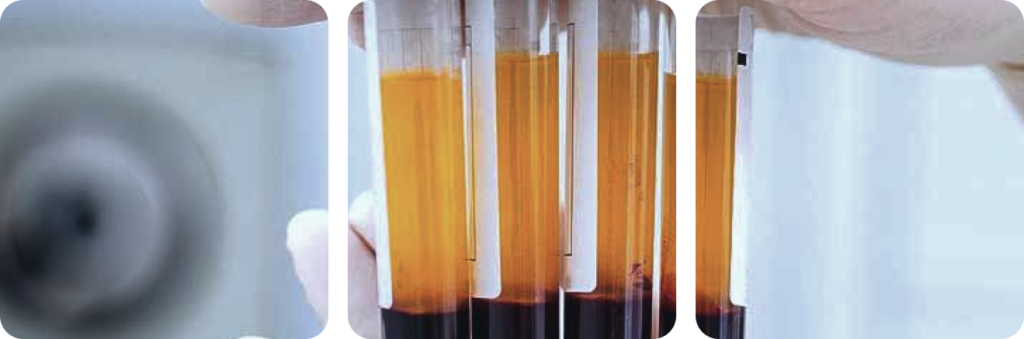

1. Blood Collection and Processing

A small amount of your blood is drawn and carefully processed in a centrifuge to concentrate the platelets and growth factors.